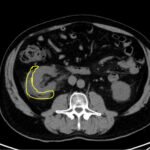

The patient is a 66-year-old male, with a history of kidney stones, who presents to the emergency department complaining of dull, right-sided flank pain radiating to the right testicle that began one hour prior to arrival. The patient had a computed tomography (CT) of the abdomen and pelvis without contrast, which demonstrated a right renal calculus with forniceal rupture. This case represents a rare complication of a typical Emergency Department complaint; therefore, clinicians should be aware of its clinical relevance.

Flank pain, forniceal rupture, renal colic, CT scan.